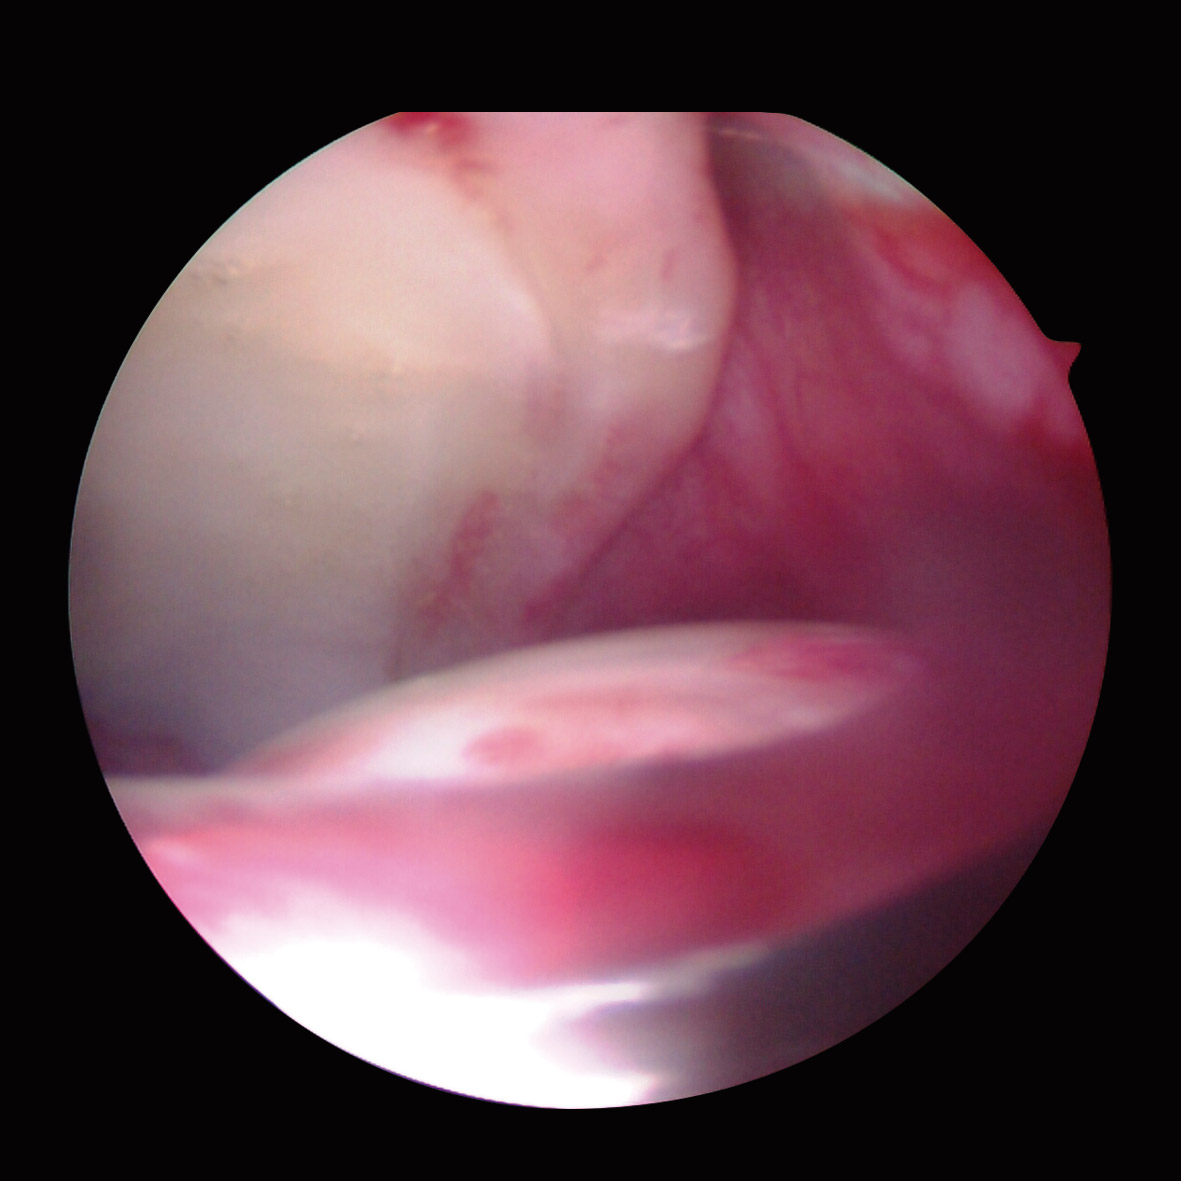

Las cirugías se realizaron con anestesia espinal, según técnica quirúrgica descrita previamente(20). Las lesiones del labrum acetabular se clasificaron según la clasificación propuesta por el grupo Multicenter Arthroscopic Hip Outcome Research Network (MAHORN)(21), que establece 4 categorías: labrum normal, labrum hipoplásico/hiperplásico, rotura del labrum y lesiones intrasustancia del labrum. La rotura del labrum se subclasificaba en rotura compleja degenerativa, separación condrolabral, rotura parcial, rotura completa y lesión de tipo flap, y las lesiones intrasustancia se subclasificaban en mucoide o amarillo, blando, hemático, osificado y calcificado. Para la localización de la lesión se utilizó el método geográfico descrito por Illizaliturri et al.(22).

Artroscópicamente, el tipo de CFA era mixto en 86 caderas (52,7%), de tipo Cam en 67 (41,1%) y de tipo Pincer en 10 (6,2%). El labrum presentaba una morfología normal (Figura 1) en 140 caderas (85,9%), hipoplásico (Figura 2) en 17 (9,8%) e hiperplásico (Figura 3) en 6 (4,3%). Se detectó algún grado de rotura del labrum en 133 caderas (81,6%); de ellas, en 98 caderas (60,1%) eran separaciones condrolabrales (Figura 4), en 26 (15,9%) roturas complejas-degenerativas (Figura 5), en 5 (3,0%) roturas parciales y en 4 (2,4%) roturas completas. El labrum presentaba cambios intrasustancia en 30 caderas (18,4%), distinguiendo en 19 (63,3%) calcificado, 9 (30%) hemático (Figura 6) y 2 (6,6%) mucoide-amarillo.